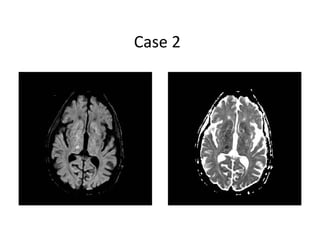

Case 2

• 85 year old male who woke up with left face, arm, and leg

numbness

• History of HTN, DM, and tobacco use

• Meds: Insulin, aspirin

• BP- 168/96, P– 92

• General exam: Unremarkable, RRR

• NEURO EXAM:

- Decreased sensation on left face, arm, and leg

Answer

• Right thalamic lacunar infarct

• Not a candidate for intervention

• Discharged to rehab 72 hours after admission